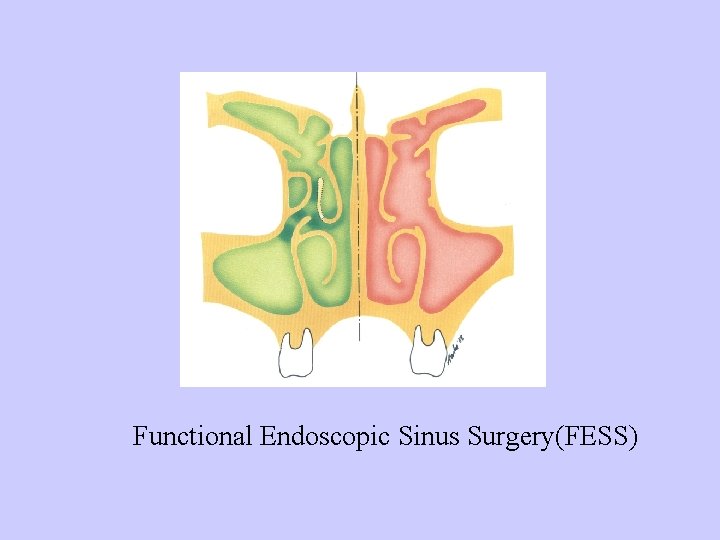

Treatment: 1、Intranasal medications:Corticosteroid, Vasoconstrictor sympasthomimetics 2、Puncture and irrigation of maxillary sinus 3、Displacement method——frontal sinusitis, ethmoidal sinusitis, sphenoidal sinusitis, pansinusitis 4、Surgery——traditional sinus surgery Functional Endoscopic Sinus Surgery(FESS) Ostiometal complex OMC

Functional Endoscopic Sinus Surgery(FESS)